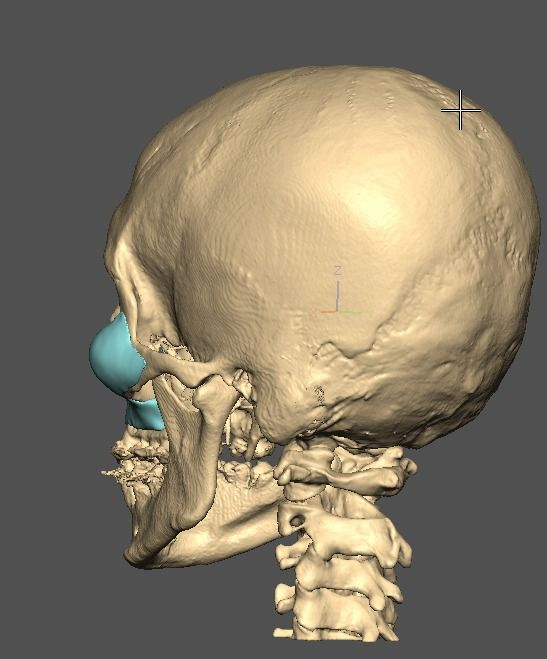

A lot changed since the initial design

current

It's going to be split into either 5 or 7 pieces.

current

It's going to be split into either 5 or 7 pieces.